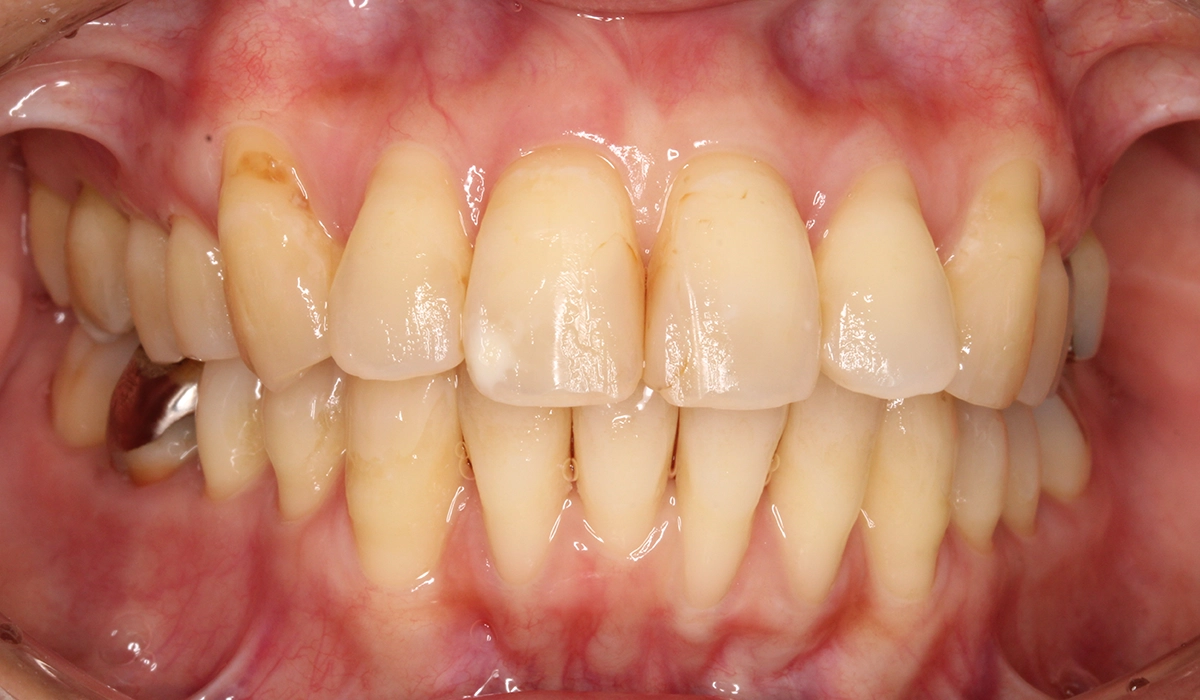

今回ご紹介する患者様は、全体的な歯のがたつきを気にされており、矯正検査後Ⅰ級叢生と診断。抜歯適応症例だが患者様希望により歯肉退縮を許容したうえで非抜歯で仕上げている。

術後:正面

| 主訴 | 全体的な歯のがたつきを気になる |

| 治療期間 | 24カ月 |

| 治療費用 | 990,000円(税込) |

| 治療内容 | 患者様は全体的な歯のがたつきを気にされており、矯正検査後Ⅰ級叢生と診断。抜歯適応症例だが患者希望により歯肉退縮を許容したうえで非抜歯で仕上げている。 |